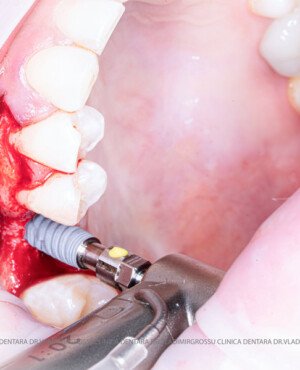

După extracția dentară, în intervalul de 6-12 luni, osul alveolar suferă un proces natural de remodelare, ceea ce conduce la scăderea volumului osos prin rezorbție. De aceea, inserția implantului dentar este ideală imediat după extracție sau, cel târziu, în primele 3-4 luni după aceasta.Scopul procedurilor de adiție osoasă este refacerea fundației osoase necesare pentru stabilizarea corectă a implantului dentar. Pentru ca un implant să reziste în timp la forțele masticatorii, este nevoie de o bază osoasă solidă și sănătoasă.

Procesul de refacere osoasă este complex, însă, simplificat, se bazează pe faptul că osul adăugat se integrează treptat, fiind înlocuit parțial cu os natural, oferind astfel suportul necesar implantului.

Adiția osoasă are un rol crucial pentru poziționarea corectă și stabilă a implanturilor dentare. Clinica stomatologică Dr. Grossu din Chișinău promovează o abordare chirurgicală estetică și predictibilă, adaptată fiecărui caz în parte.